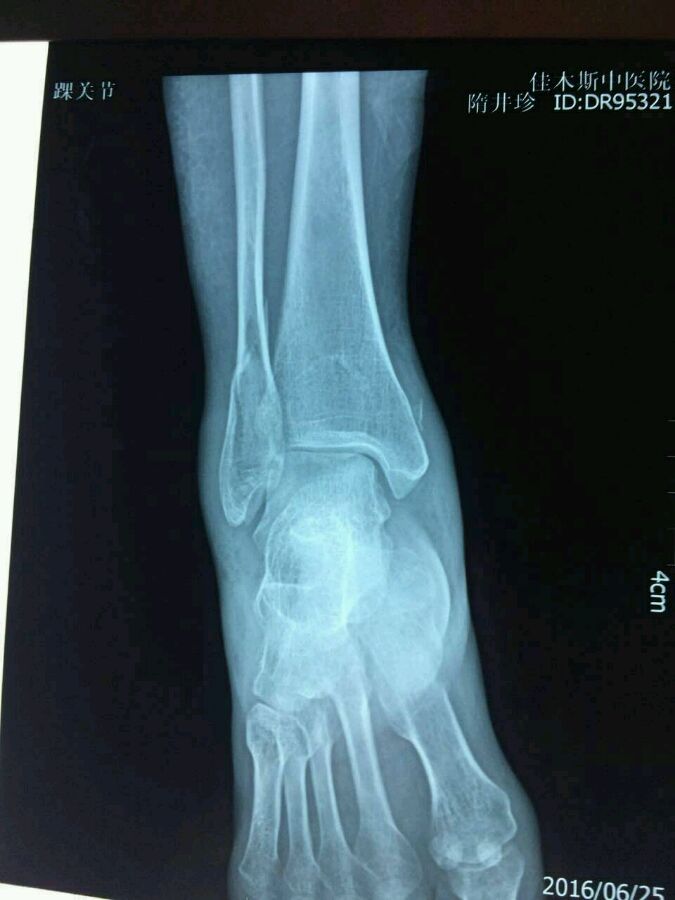

57岁,昨天滑倒骨折,刚拍的片子,主任看看能否保守治疗

片子没有完全传上了您再看看,后踝也有骨折